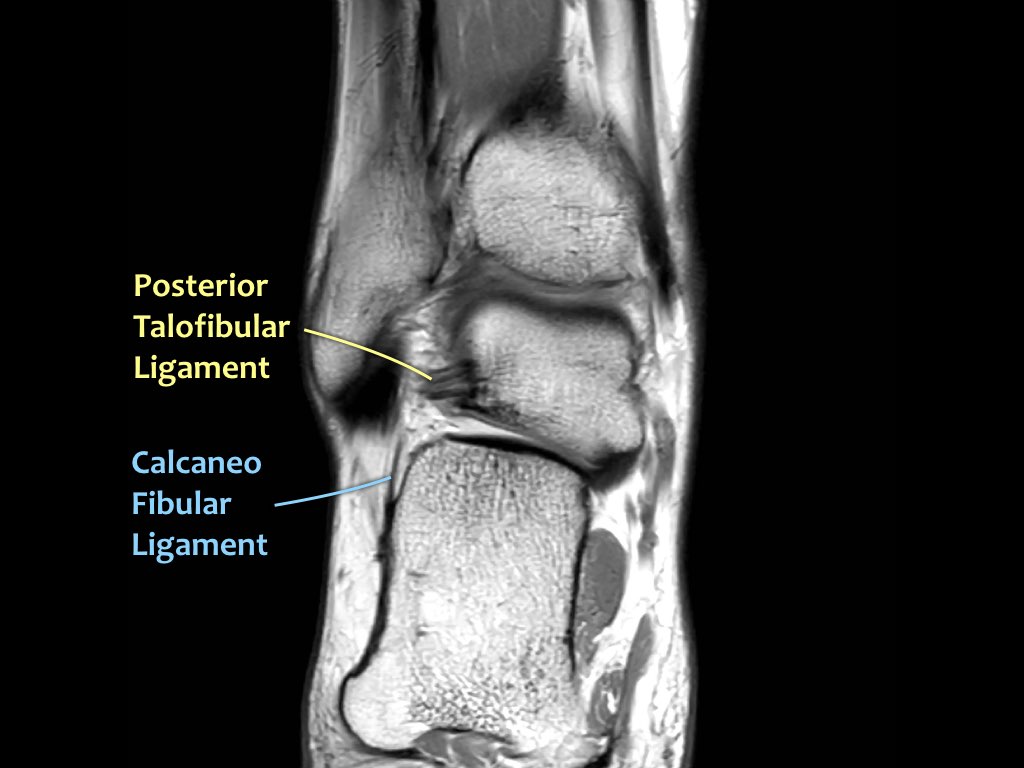

Có ba dây chằng ở phía ngoài:

- Dây chằng sên mác trước (anterior talofibular ligament – ATFL)

- Dây chằng gót mác (calcaneofibular ligament – CFL)

- Dây chằng sên mác sau (posterior talofibular ligament – PTFL).

Dây chằng ATFL chạy từ mắt cá ngoài ra phía trước đến bờ ngoài của xương sên.

Dây chằng này có hướng nằm ngang và được quan sát rõ nhất trên ảnh cắt ngang.

Đây là dây chằng bị tổn thương thường gặp nhất ở cổ chân và cũng là dây chằng đầu tiên bị tổn thương ở phía ngoài.

Điều này có nghĩa là khi dây chằng CFL hoặc PTFL bị tổn thương, rất có khả năng dây chằng ATFL cũng đã bị tổn thương.